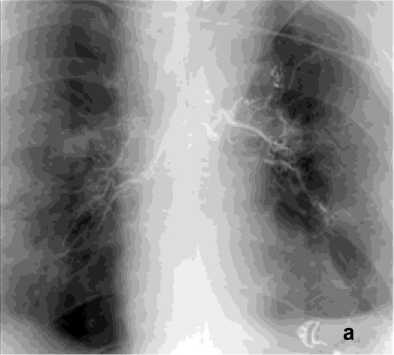

Эмболизация бронхиальных артерий (ЭБА) является радикальным методом лечения ЛК из системы бронхиальных артерий и выполнена в 134 (89,9%) cлучаях. ЭБА часто считается первой линией лечения при массивном ЛК. Эмболизация правой бронхиальной артерии проведена в 68 (45,1%) случаях, левой – в 32 (21,1%), обеих бронхиальных артерий - в 34 (22%) случаях (рис. 6).

Рисунок 6. Ангиограмма БА у пациента с опухолью заднего средостения и прорастанием лёгкого, ЛК2Б: а – извитость и усиление лёгочного рисунка; б – состояние после эмболизации – окклюзия БА

Figure 6. Angiogram of the BA in a patient with posterior mediastinal tumor and lung invasion, PH grade 2B: a – tortuosity and increased pulmonary vascularity; б – status post embolization – occlusion of the BA

Предполагаемые источники кровотечения эм-болизированы с помощью микросфер, желатиновых губок и спиралей (рис. 8, а, б). Комбинированное применение эндобронхиальной тампонады с эмболизацией бронхиальных артерий выполнено у 13 (8,7%) пациентов и позволило во всех случаях добиться прекращения поступления крови в трахеобронхиальное дерево и избежать асфиксии (рис. 8, в, г).

Рецидив ЛК после эмболизации наблюдался у 15 (10%) пациентов, в 3 случаях из них эмболизация БА была выполнена более года назад. В результате ангиографического поиска выявлены дополнительные источники ЛК: межреберные артерии – 4, внутренняя грудная артерия – 8 (рис. 8), АV – 3 (рис. 7).